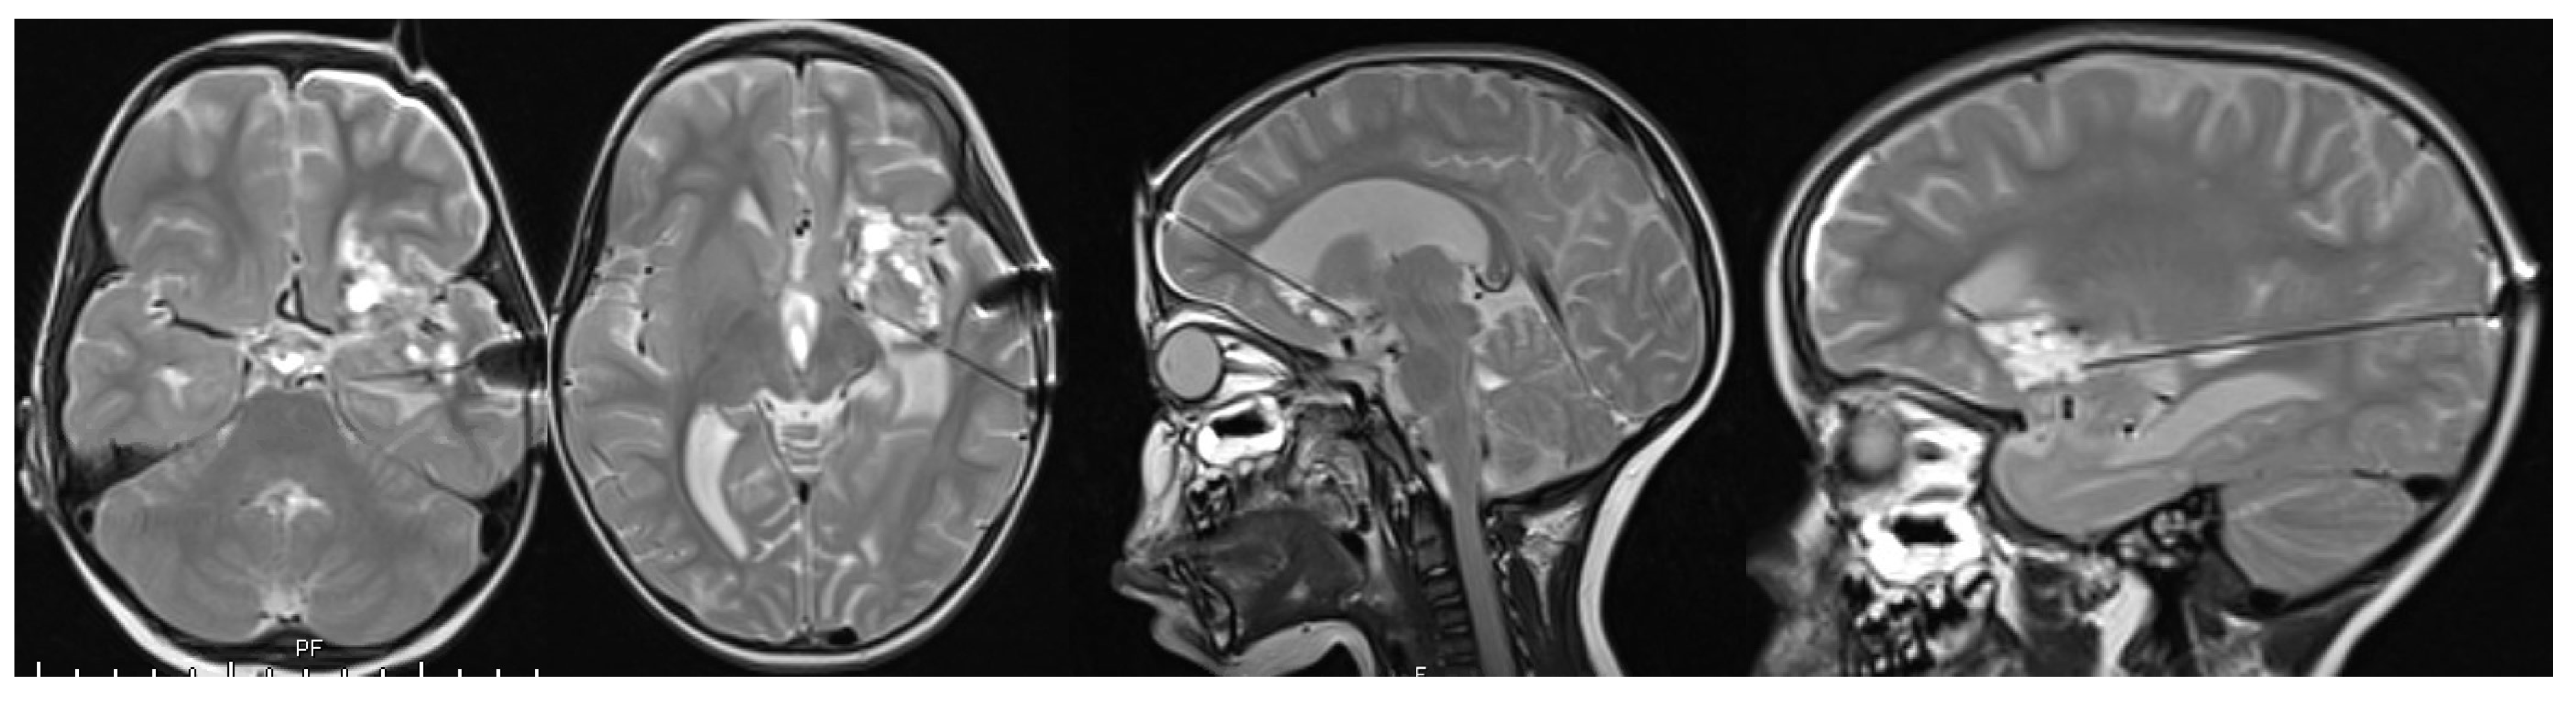

Case Report